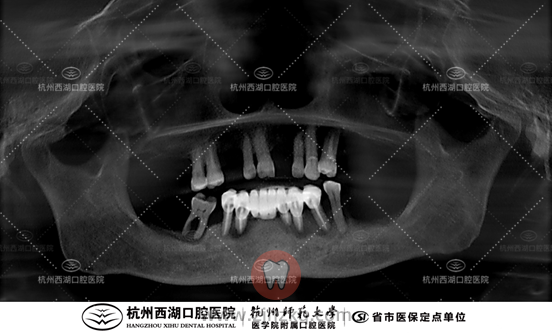

术后CBCT照如下